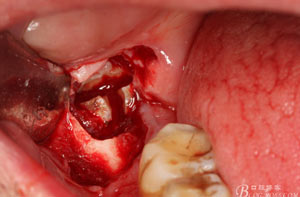

圖9.高速牙鉆分牙:

圖10.先頰舌向橫斷、然后再把牙冠近遠(yuǎn)中向縱分

圖11. “T”型的分牙。